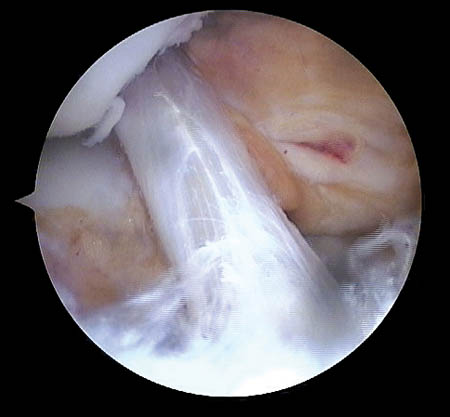

Respecto a su morfología usamos la clasificación de Lage et al.28 (Figs. 9, 10 y 11) que se distribuyeron de la siguiente manera:

Figura 9: Lesión labral fibrilar.

Figura 10: Lesión labral por mecanismo Pincer.

Figura 11.